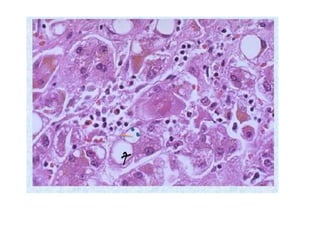

The document summarizes key aspects of liver and gallbladder anatomy and histology. It notes that hepatocytes in the liver have abundant mitochondria and are surrounded by peri-sinusoidal spaces filled with microvilli. The gallbladder stores and concentrates bile produced by the liver through absorption and secretion. The gallbladder can become inflamed or damaged due to blockage and accumulation over time.